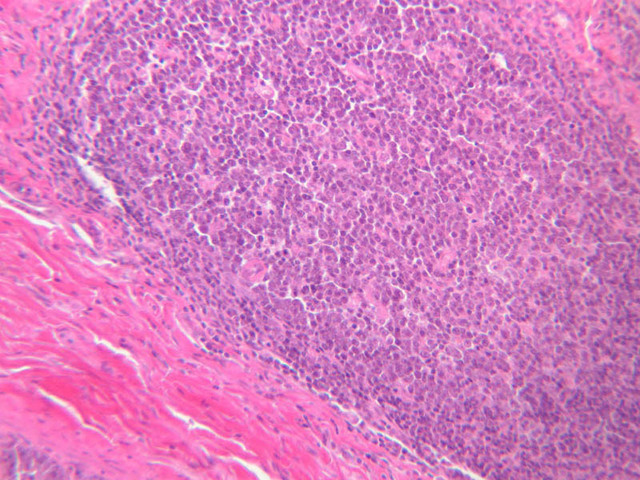

The structure of sinusoids can be studied in the liver (B-29, H&E [10x, 20x, 40x] [10x-labeled, 20x, 40x-labeled]; B-30, H&E [10x, 20x, 40x]; B-35, PAS [10x, 20x, 40x]) where they occur as endothelial tubes between plates of hepatocytes. In the liver, they are channels slightly larger in diameter than red blood cells and the individual lining cells have open spaces between them. The principal difference between sinusoids and capillaries is size, which presumably allows blood to flow more slowly in the larger sinusoids.

B12, Jejunum, 10x (H&E) B12, Jejunum, 20x (H&E) B12, Jejunum, 40x Labeled (H&E) B12, Jejunum, 2.5x (H&E) B12, Jejunum, 10x (H&E) B12, Jejunum, 20x (H&E) B12, Jejunum, 40x (H&E) B13, Jejunum, 2.5x (PAS) B13, Jejunum, 10x (PAS) B13, Jejunum, 20x Labeled (PAS) B13, Jejunum, 40x (PAS) B15, Jejunum, 2.5x (H&E) B15, Jejunum, 10x (H&E) B15, Jejunum, 20x (H&E) B15, Jejunum, 40x (H&E) B15, Jejunum, 2.5x (H&E) B15, Jejunum, 10x (H&E) B15, Jejunum, 20x (H&E) B15, Jejunum, 40x (H&E) B15, Jejunum, 10x (H&E) B15, Jejunum, 20x (H&E) B15, Jejunum, 40x (H&E) B16, Ileum, 10x (H&E) B16, Ileum, 20x (H&E) B16, Ileum, 40x Labeled (H&E) B16, Ileum, 2.5x (H&E) B16, Ileum, 10x (H&E) B16, Ileum, 20x (H&E) B16, Ileum, 40x (H&E) B23, Colon, 2.5x (H&E) B23, Colon, 10x (H&E) B23, Colon, 20x Labeled (H&E) B23, Colon, 40x (H&E) B24, Colon, 2.5x (H&E) B24, Colon, 10x (H&E) B24, Colon, 20x (H&E) B24, Colon, 40x Labeled (H&E) B26, Rectal-Anal Junction, 2.5x (H&E) B26, Rectal-Anal Junction, 10x (H&E) B26, Rectal-Anal Junction, 20x (H&E) B26, Rectal-Anal Junction, 40x (H&E) B26, Rectal-Anal Junction, 2.5x (H&E) B26, Rectal-Anal Junction, 10x (H&E) B26, Rectal-Anal Junction, 20x (H&E) B26, Rectal-Anal Junction, 40x Labeled (H&E) A48, Abdominal Skin, 2.5x (H&E) A48, Abdominal Skin, 10x (H&E) A48, Abdominal Skin, 20x (H&E) A48, Abdominal Skin, 40x (H&E) A50, Fingertip, 2.5x (H&E) A50, Fingertip, 10x (H&E) A50, Fingertip, 20x (H&E) A50, Fingertip, 40x (H&E) A50, Fingertip, 2.5x (H&E) A50, Fingertip, 10x (H&E) A50, Fingertip, 20x (H&E) A50, Fingertip, 40x (H&E) A50, Fingertip, 2.5x (H&E) A50, Fingertip, 10x (H&E) A50, Fingertip, 20x (H&E) A50, Fingertip, 40x (H&E) A58, Axillary Skin, 2.5x (H&E) A58, Axillary Skin, 10x (H&E) A58, Axillary Skin, 20x (H&E) A58, Axillary Skin, 40x Labeled (H&E) B29, Liver (Sinusoids), 10x (H&E) B29, Liver (Sinusoids), 20x (H&E) B29, Liver (Sinusoids), 40x (H&E) B29, Liver (Sinusoids), 10x Labeled (H&E) B29, Liver (Sinusoids), 20x (H&E) B29, Liver (Sinusoids), 40x Labeled (H&E) B30, Liver (Sinusoids), 10x (H&E) B30, Liver (Sinusoids), 20x (H&E) B30, Liver (Sinusoids), 40x (H&E) B35, Liver (Sinusoids), 10x (PAS) B35, Liver (Sinusoids), 20x (PAS) B35, Liver (Sinusoids), 40x (PAS)